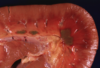

Acute renal infarct

Acute renal infarct after 2-3d

infarct of an entire kidney

large renal infarct